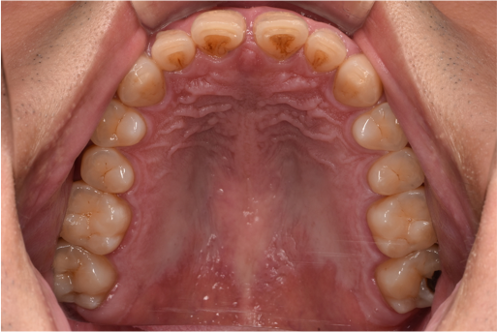

| カウンセリング・診断結果 | こちらの患者様は1日20本ほどタバコを吸われる方で、歯医者は十数年振りとのことでした。 縁上歯石と全体的に縁下歯石が付着しており、歯ぐきが赤く腫れ炎症しておりました。前歯の歯頸部や裏側に着色も認められました。歯周病検査により中等度の歯周炎が認められたため歯周治療も必要でした。 |

| 行ったご提案・治療内容 | 初診時はブラッシング方法などセルフケアについて説明を行い、縁上歯石・着色の除去を行いましました。 歯肉の炎症がある程度落ち着いたところで、後日再評価を行い歯周治療へ移行しました。 |